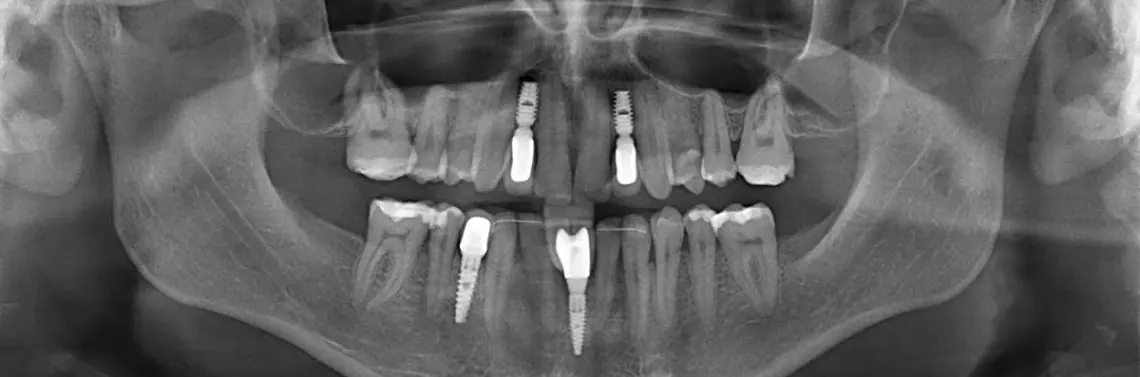

Mianem hipodoncji określa się zwykle wrodzony brak jednego bądź kilku zębów, co należy do częstych wad rozwojowych uzębienia. Może występować sporadycznie lub być dziedziczny. Często współistnieje z innymi nieprawidłowościami zębowymi, takimi jak zaburzenia morfologii, zmiany położenia zębów, opóźnienie ząbkowania. W naszym przypadku był to izolowany brak zębów (zdj. 1, 2, 3, 4) oraz przetrwałe siekacze dolne mleczne przy braku zawiązków zębów stałych.

Zdjęcie pantomograficzne wykazało wrodzony brak zębów 12, 22, 41, 31 i 44 oraz przestrzenie pomiędzy innymi zębami. Nieobecne są również drugie i trzecie trzonowce górne i dolne (zdj. 1).

Po roku od rozpoczęcia leczenia ortodontycznego uzyskano wystarczającą przestrzeń dla wszczepienia górnych bocznych siekaczy. Procedurę chirurgiczną przeprowadzono w znieczuleniu miejscowym. Wykonano cięcia na szczycie wyrostka zębodołowego szczęki w okolicy 12 i 22. Po delikatnym odpreparowaniu tkanek miękkich utworzono łoże dla implantów, stosując technikę rozszczepienia wyrostka zębodołowego dłutami firmy Bicon oraz technikę osteotomową w połączeniu z wiertłami niskoobrotowymi z zestawu, bez stosowania chłodzenia wodnego. W trakcie wiercenia uzyskuje się wióry kostne służące potem do augmentacji ponad wszczepionym implantem. Postępowanie takie ma na celu poprawę parametrów objętościowych kości oraz estetyki wyrostka w okolicy uprzednio pozbawionej korzeni. Brak zabiegu w pełnym płacie nastręcza pewne problemy i wymaga dużego doświadczenia operującego. Dzięki brakowi materiałów kościozastępczych i ograniczeniu rozległości zabiegu pozwala jednak skrócić czas oczekiwania na gojenie. Nie bez znaczenia jest niska prędkość obrotowa w trakcie wiercenia, a co za tym idzie – brak konieczności stosowania chłodzenia wodnego wypłukującego czynniki gojenia z tkanki. Zwiększa się też komfort pacjenta. W pozycji 12 i 22 zastosowano wszczepy Bicon 4,8/8 o studni średnicy 2,5 mm (zdj. 7).

Ze względu na brak podatności na przesuwanie zębów dolnych w odcinku przednim w celu odtworzenia prawidłowej szerokości na dwa brakujące siekacze zdecydowano się na wszczepienie jednego implantu i późniejsze protezowanie koronami zblokowanymi na jednym łączniku. Zabieg ze względu na próby ortodontyczne nastąpił 10 miesięcy od augmentacji (implant MIS c1, 3,75/11,5). W jego trakcie stwierdzono prawie całkowitą resorpcję materiału oraz szeroki wyrostek zębodołowy.

W górnym łuku po odsłonięciu implantów zastosowano anatomiczne śruby gojące przez trzy tygodnie. Postępowanie protetyczne obejmowało wyciski wykonane z masy wyciskowej Impregum. Zastosowano łączniki metalowe oraz korony na podbudowie metalowej z frezowanego stopu Sintron. Dzięki specyfice systemu Bicon korony zostały zacementowane na łącznikach poza jamą ustną i zamontowane jako zintegrowany zespół z łącznikiem (zdj. 8).

Cztery miesiące po zamontowaniu koron bocznych górnych siekaczy odsłonięto implanty w dolnym łuku (zdj. 9, 10). Faza protetyczna została przeprowadzona w okresie gojenia zamkniętego implantów. Wykorzystano śruby anatomiczne. Wykonano indywidualnie ukształtowaną koronę odwzorowującą wygląd dwóch centralnych siekaczy dolnych z wykorzystaniem różowej ceramiki imitującej brodawkę międzyzębową (zdj. 11, 12).